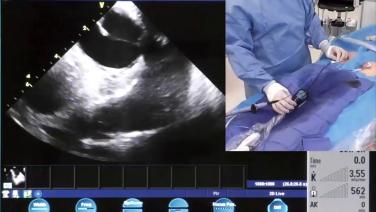

Utilizing Intracardiac Echo During Transseptal Puncture with Brett Gidney, MD

Identifying Left Atrial Anatomy using Intracardiac Echo for Transseptal Puncture with James Brian Deville, MD

ICE Views for Atrial Flutter & Ventricular Structures with Andrew Brenyo, MD